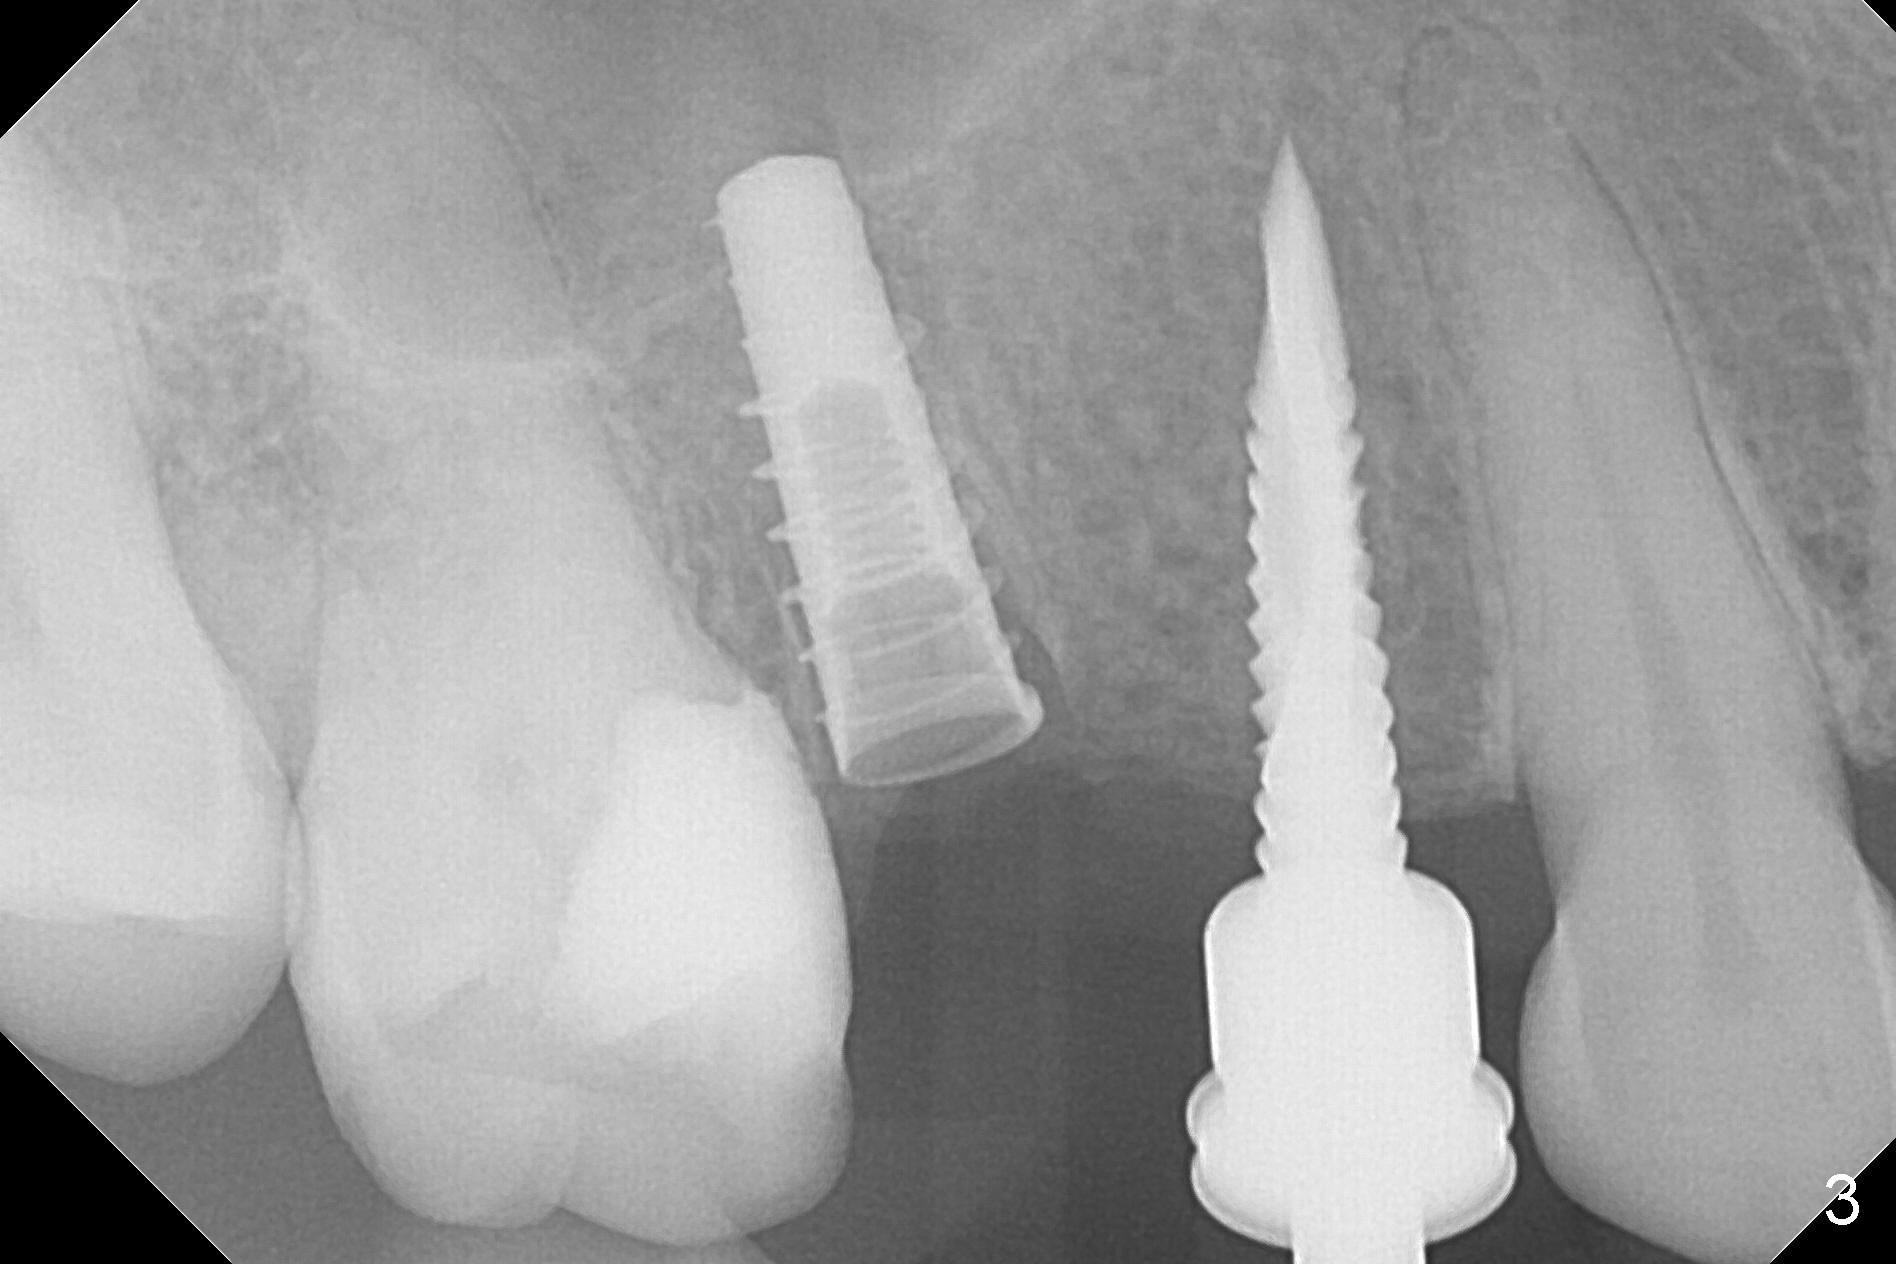

The buccal plate of the socket of #4 is thin and short (Fig.1, 5B (coronal section of the socket) red area) with apical perforation (Fig.5B >). Osteotomy at #4 starts with 1.6 mm drill in the palatal slope (Fig.2 circle; Fig.5C blue arrow), while that at #5 with Magic Split (Fig.2 black line). In fact sinus perforation occurs with the 1.6 mm drill. Osteotomy increases by using Magic Drills sequentially (2.8 and 3.3 mm) at #4 and Magic expander (3.0 mm) and the same Magic Drills at #5 (Fig.3). A 4x11 mm dummy IBS implant is placed with insertion torque of 45 Ncm at #4 with apparently intruding into the sinus (Fig.3). When a 4.5x9 mm implant is placed, the insertion torque is actually reduced (<35 Ncm, Fig.4). As osteotomy or implant diameter enlarges, it shifts buccally with less bone contact buccally (Fig.5D, as compared to Fig.5C)). In brief, once a dummy implant has achieved a reasonably high stability, do not over seat it. A small immediate implant may have more solid bone contact.